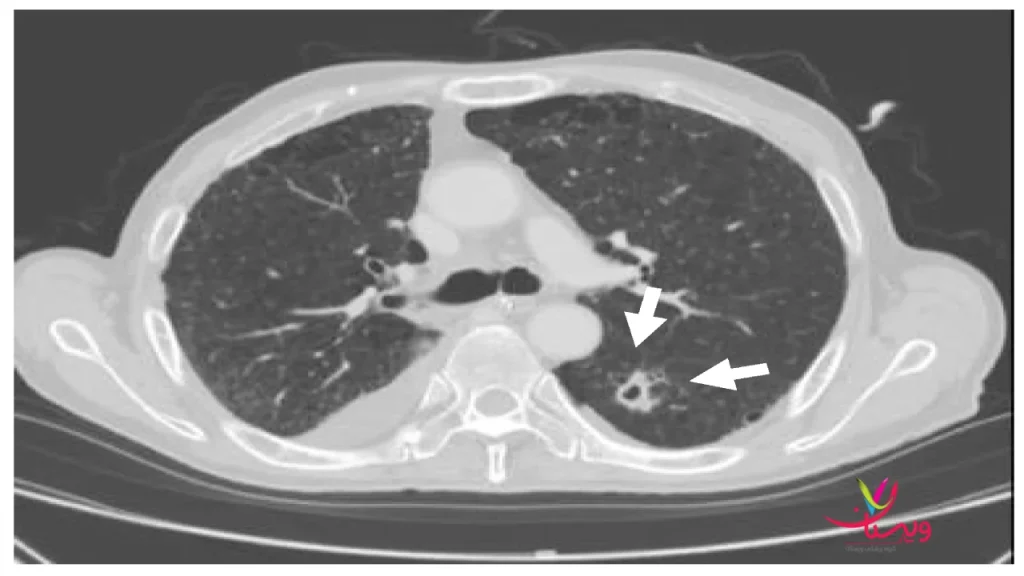

۳. اسکن ید کلبدن در سرطان تیروئید

برای بیماران مبتلا به سرطان تیروئید، اسکن ید کلبدن معمولاً بعد از درمان با ید رادیواکتیو انجام میشود تا بافت باقیمانده یا متاستازها بررسی شود. در این شرایط، اسکن هستهای تیروئید اطلاعات دقیق از عملکرد غده و مناطق مشکوک ارائه میدهد و به برنامه درمانی فرد کمک میکند.

با ترکیب اسکن هستهای تیروئید و روشهای مکمل، پزشک میتواند تصویر جامع و دقیقی از وضعیت تیروئید بیمار بهدست آورد و بهترین مسیر درمانی را انتخاب کند.